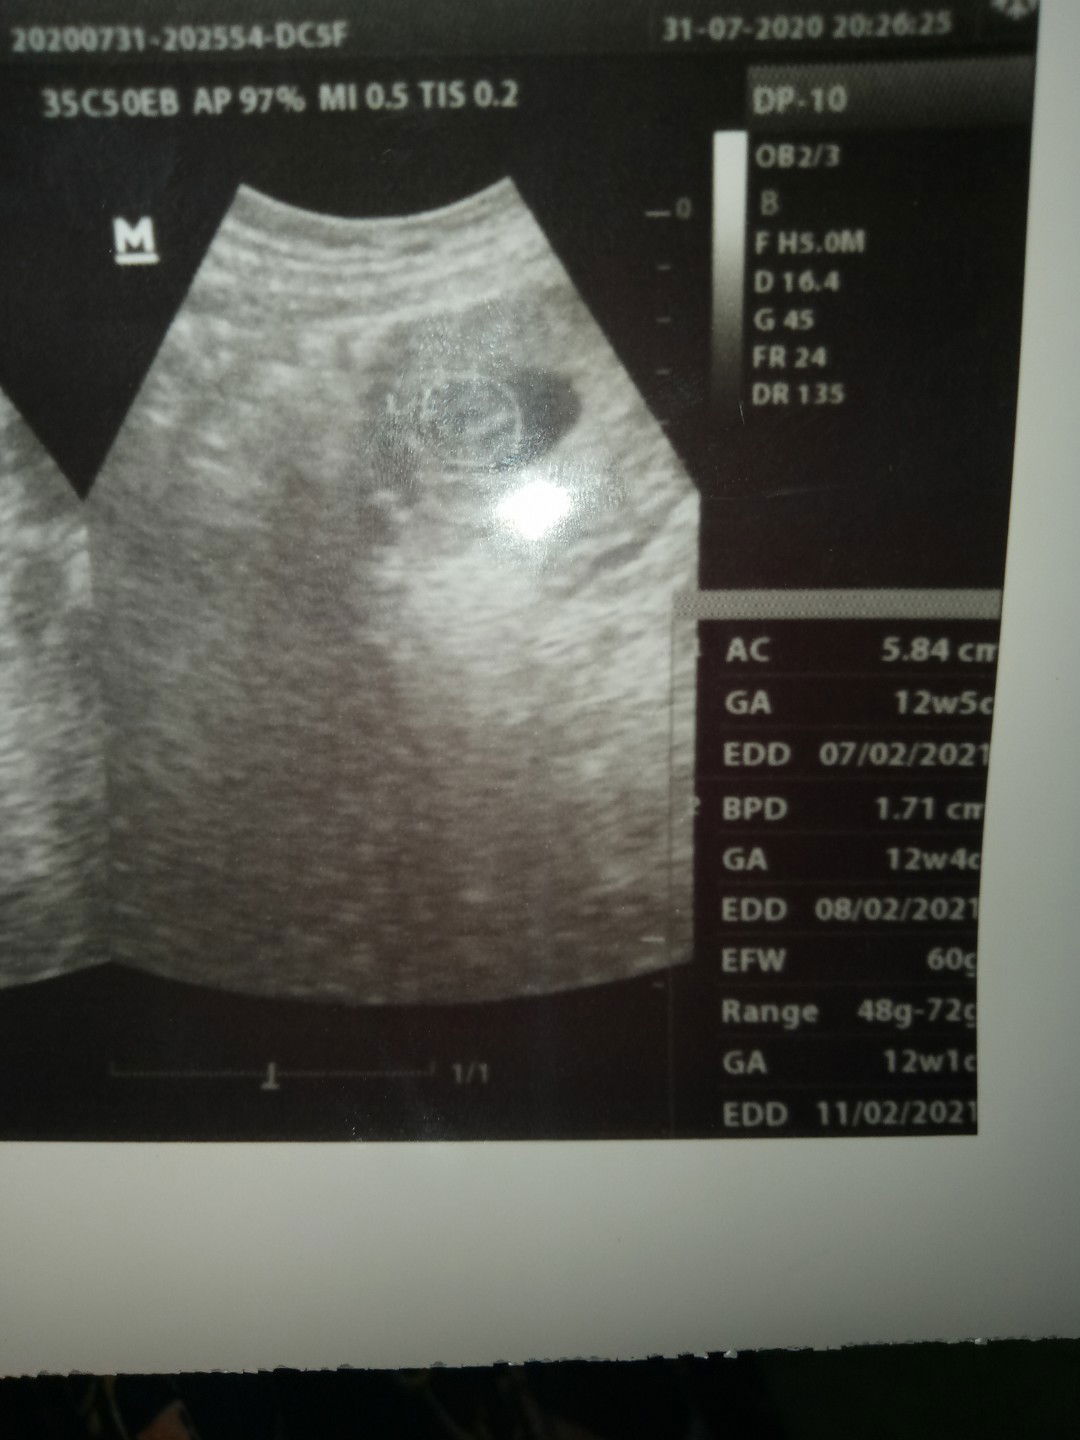

berat badan janin

bunda aku hamil 12week5day berat badan janin ku 60grm apa kah normal atau gmn?